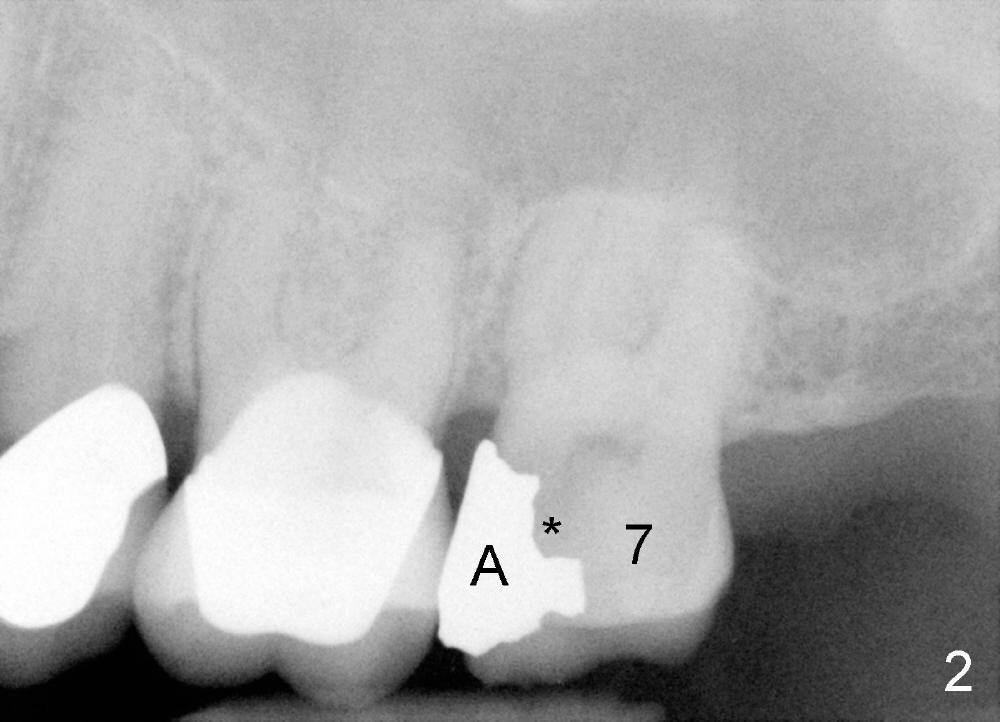

陈先生五十来岁,牙齿不好,右上有一个三个单位桥(图一:5-7),右下四个单位桥(5-8)。五年前他第一次来诊所时左上7有牙髓炎症状(图二),那颗牙齿有很大银汞充填物(A),之下出现龋齿(*)。出于救死护伤精神,开始做根管治疗(图三:*牙胶尖),当时他原来牙医出差了,之后给左上7戴上牙冠(图四:C)。其实图四X光片拍摄是在左上7根管治疗之后一年半,这次左上5有牙髓炎症状,再次为他做根管治疗(图五:*)。他又很久才回来:两年半,这次问题更严重:左上7断了(图五),好在他毫无怨言,可能与他是修理工有关,牙齿也需要修修补补。他也知道现在必须做植牙,这时我们非常自豪告诉他我们能做植牙,他便回家凑钱。一年半后他又从天降,左上问题还没有解决,右下8基牙在桥下出现龋齿(图六:^),必须拔除,这时右下6,7必须先做植牙(图六:植牙设计;N:下齿槽神经; L:颏神经襻(loop))。末端缺牙做活动义齿效果不好,据研究表明它只能恢复百分之十咀嚼功能,而植牙百分之百。